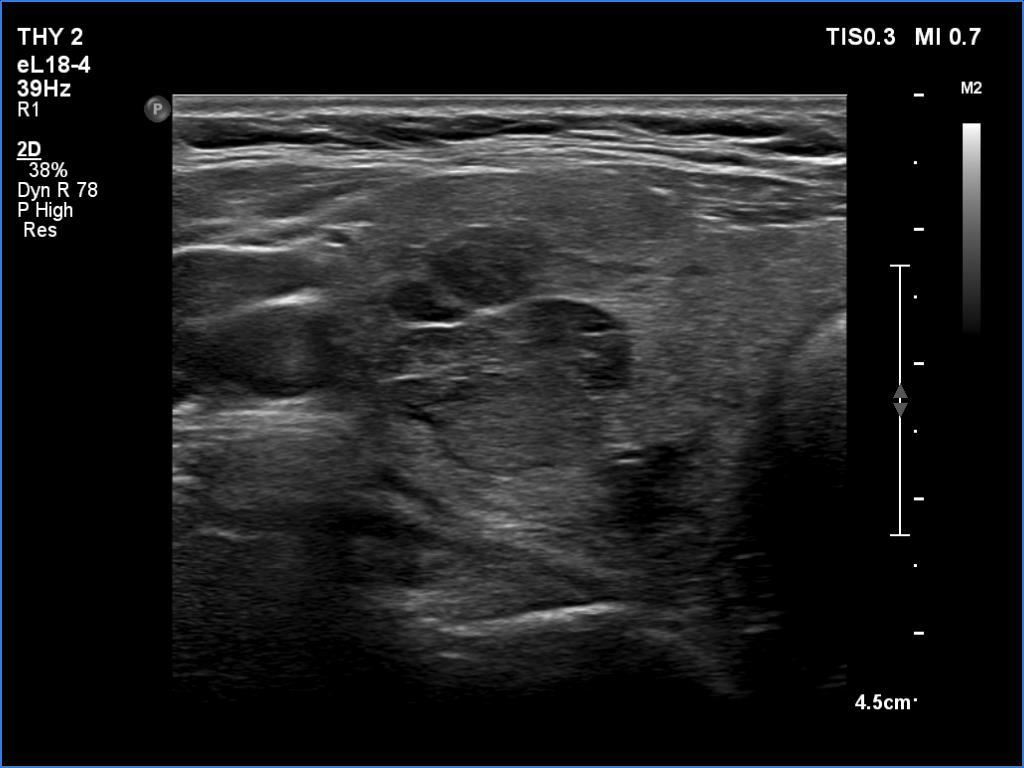

One year after the first examination (second row of images):

Clinical presentation. The patient had no complaints She came to follow-up visit.

Palpation: unchanged.

Results of blood tests: subclinical hyperthyroidism on daily 10 mg methimazole (TSH 0.001 mIU/L, FT4 13.8 pM/L, TSAb 8.2 U/L (normal value below 1.5)).

Ultrasonography. The thyroid became more hypoechoic while the lesion in the central part of the right lobe did hyperechoic. The vascularization of the thyroid was extremely increased.The patient was told that it is very likely that her hyperthyroidism will relapse therefore we suggested radioiodine therapy.